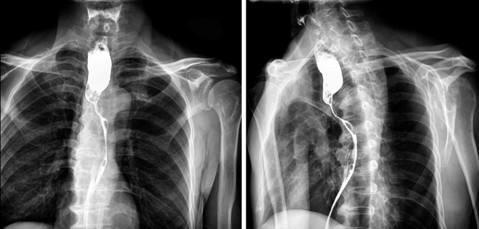

髓质型食管癌的x线表现与放疗预后的关系

按病理形态,食道癌主要可分4型: 髓质型:占70%,壁明显增厚向内扩展